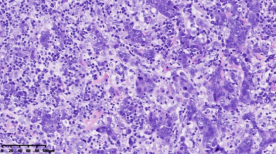

在本项研究中,研究人员利用基本的组织形态学方法及免疫组织化学法对TNBC进行分型:腔面雄激素受体型(LAR)(图1A),免疫调节型(IM)(图1B),基底样免疫抑制型(BLIS)(图1C),间充质型(MES)(图1D)。评价各亚型临床病理参数(如发病年龄、肿物大小、淋巴结转移等),组织形态学(肿物中央瘢痕形成、浸润模式、肿瘤间质浸润淋巴细胞、细胞排列方式、细胞核形态、核分裂计数、间叶化生等)以及免疫表型(p53、Rb、PD-L1、MMR等),结果显示:1.TNBC分型的临床病理、组织形态学和免疫表型特征不尽相同,有望成为复杂的基因表达谱分析的替代选择,为TNBC的分型治疗及靶向治疗提供理论依据;2.生物标记物 PD-L1作为重要的生物学指标,对个体化治疗及免疫治疗有重要的临床指导价值;3.乳腺癌中dMMR作为一个低频发生事件,不太可能作为免疫治疗有效性的评估手段。该成果发表在Virchows Archiv期刊,题目为“Subclassifying Triple-Negative Breast Cancers and Its Potential Clinical Utility”。文章DOI为:10.1007/s00428-022-03329-0。

图1. 基于组织形态学及免疫组织化学标记物的TNBC分型